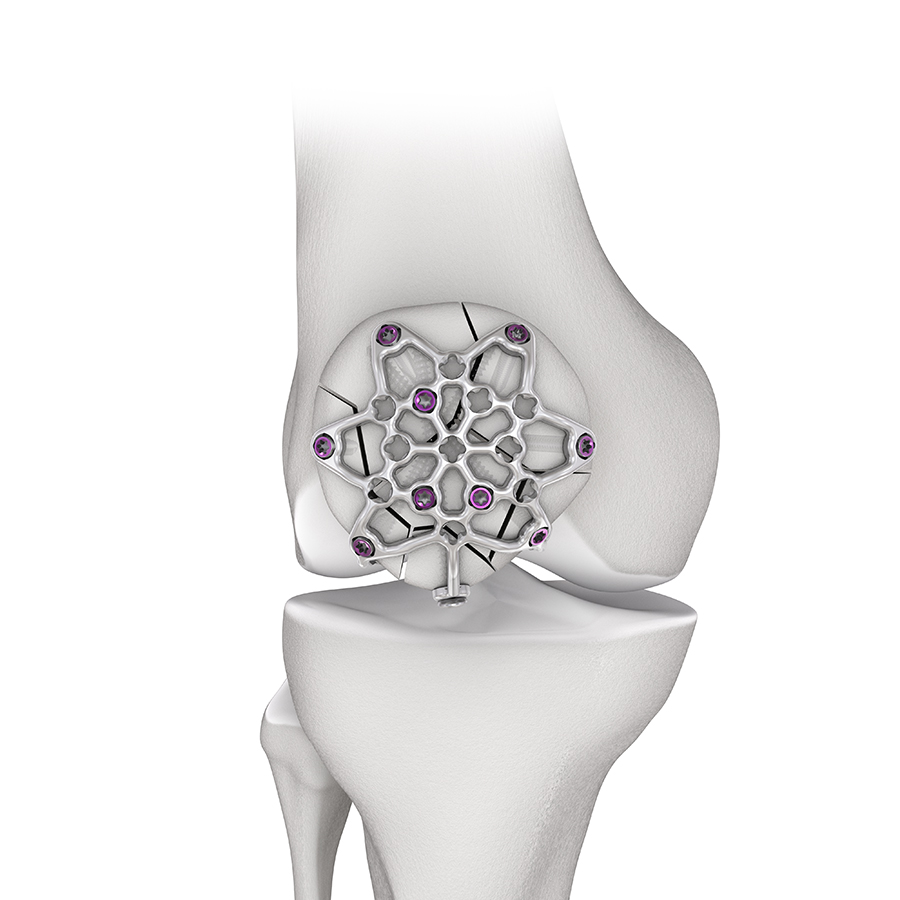

To address these issues Eladio Saura-Sanchez envisioned a dedicated, preformed anterior patella plate mimicking the structure of an ice crystal with well distributed locking hole options. In addition to a basic plate, he proposed a patella plate version with some extended plate legs that can be bent around the patella to basket and stabilize fracture fragments as required. Inspired by this vision, the 2.7 Variable Angle Locking Anterior Patella Plates (Fig 1) and instruments were developed by the PTF and LEEG in collaboration with DePuy Synthes under the medical lead of Eladio Saura-Sanchez.

The 2.7 Variable Angle Locking Anterior Patella Plates comprise six plate types (Fig 2) in stainless steel (with 1.8 mm plate thickness) and titanium (with 2.0 mm plate thickness) to address a large variety of fractures in large and small patellae. The plates leverage a smooth, low-profile mesh design to minimize soft tissue irritations, preserve blood supply and facilitate plate adaptation to the bone. While the core plates are intended to be used for simple fractures, the three-hole and six-hole plate versions can be chosen to treat more complex fracture patterns. All plates are precontoured to minimize intraoperative bending and contouring. The arms and legs can be cut to meet the needs for the specific fracture pattern and patient anatomy.

The plate consists of three plate sections (body, arms, and legs) to allow versatile plate use (Fig 3). Plate arms originate from a rigid plate body to achieve the required anterior bone coverage. The arms can be bent to adapt to the anterior patella surface. Three legs extend from the arms/body of the three-hole and six-hole plate versions. They can be oriented and bent around the patella to secure fracture fragments.

There are several plate features to ease and improve patella fracture fixation (Fig 4): variable angle (VA) locking holes enable up to 15° of screw angulation to target small bone fragments and to avoid fracture lines as well as other hardware. The screw holes accept 2.4 mm and 2.7 mm VA locking and cortex screws (2.4 mm screws are only for use in small, non-load bearing fragments). There is a tab on one of the plate arms for orientation purposes when the plate is contoured ex-situ. The tab is not required in the three-hole and six-hole plate versions since the plate legs help with proper plate orientation. The plate windows in the open architecture plate can be used to attach soft tissues with sutures.